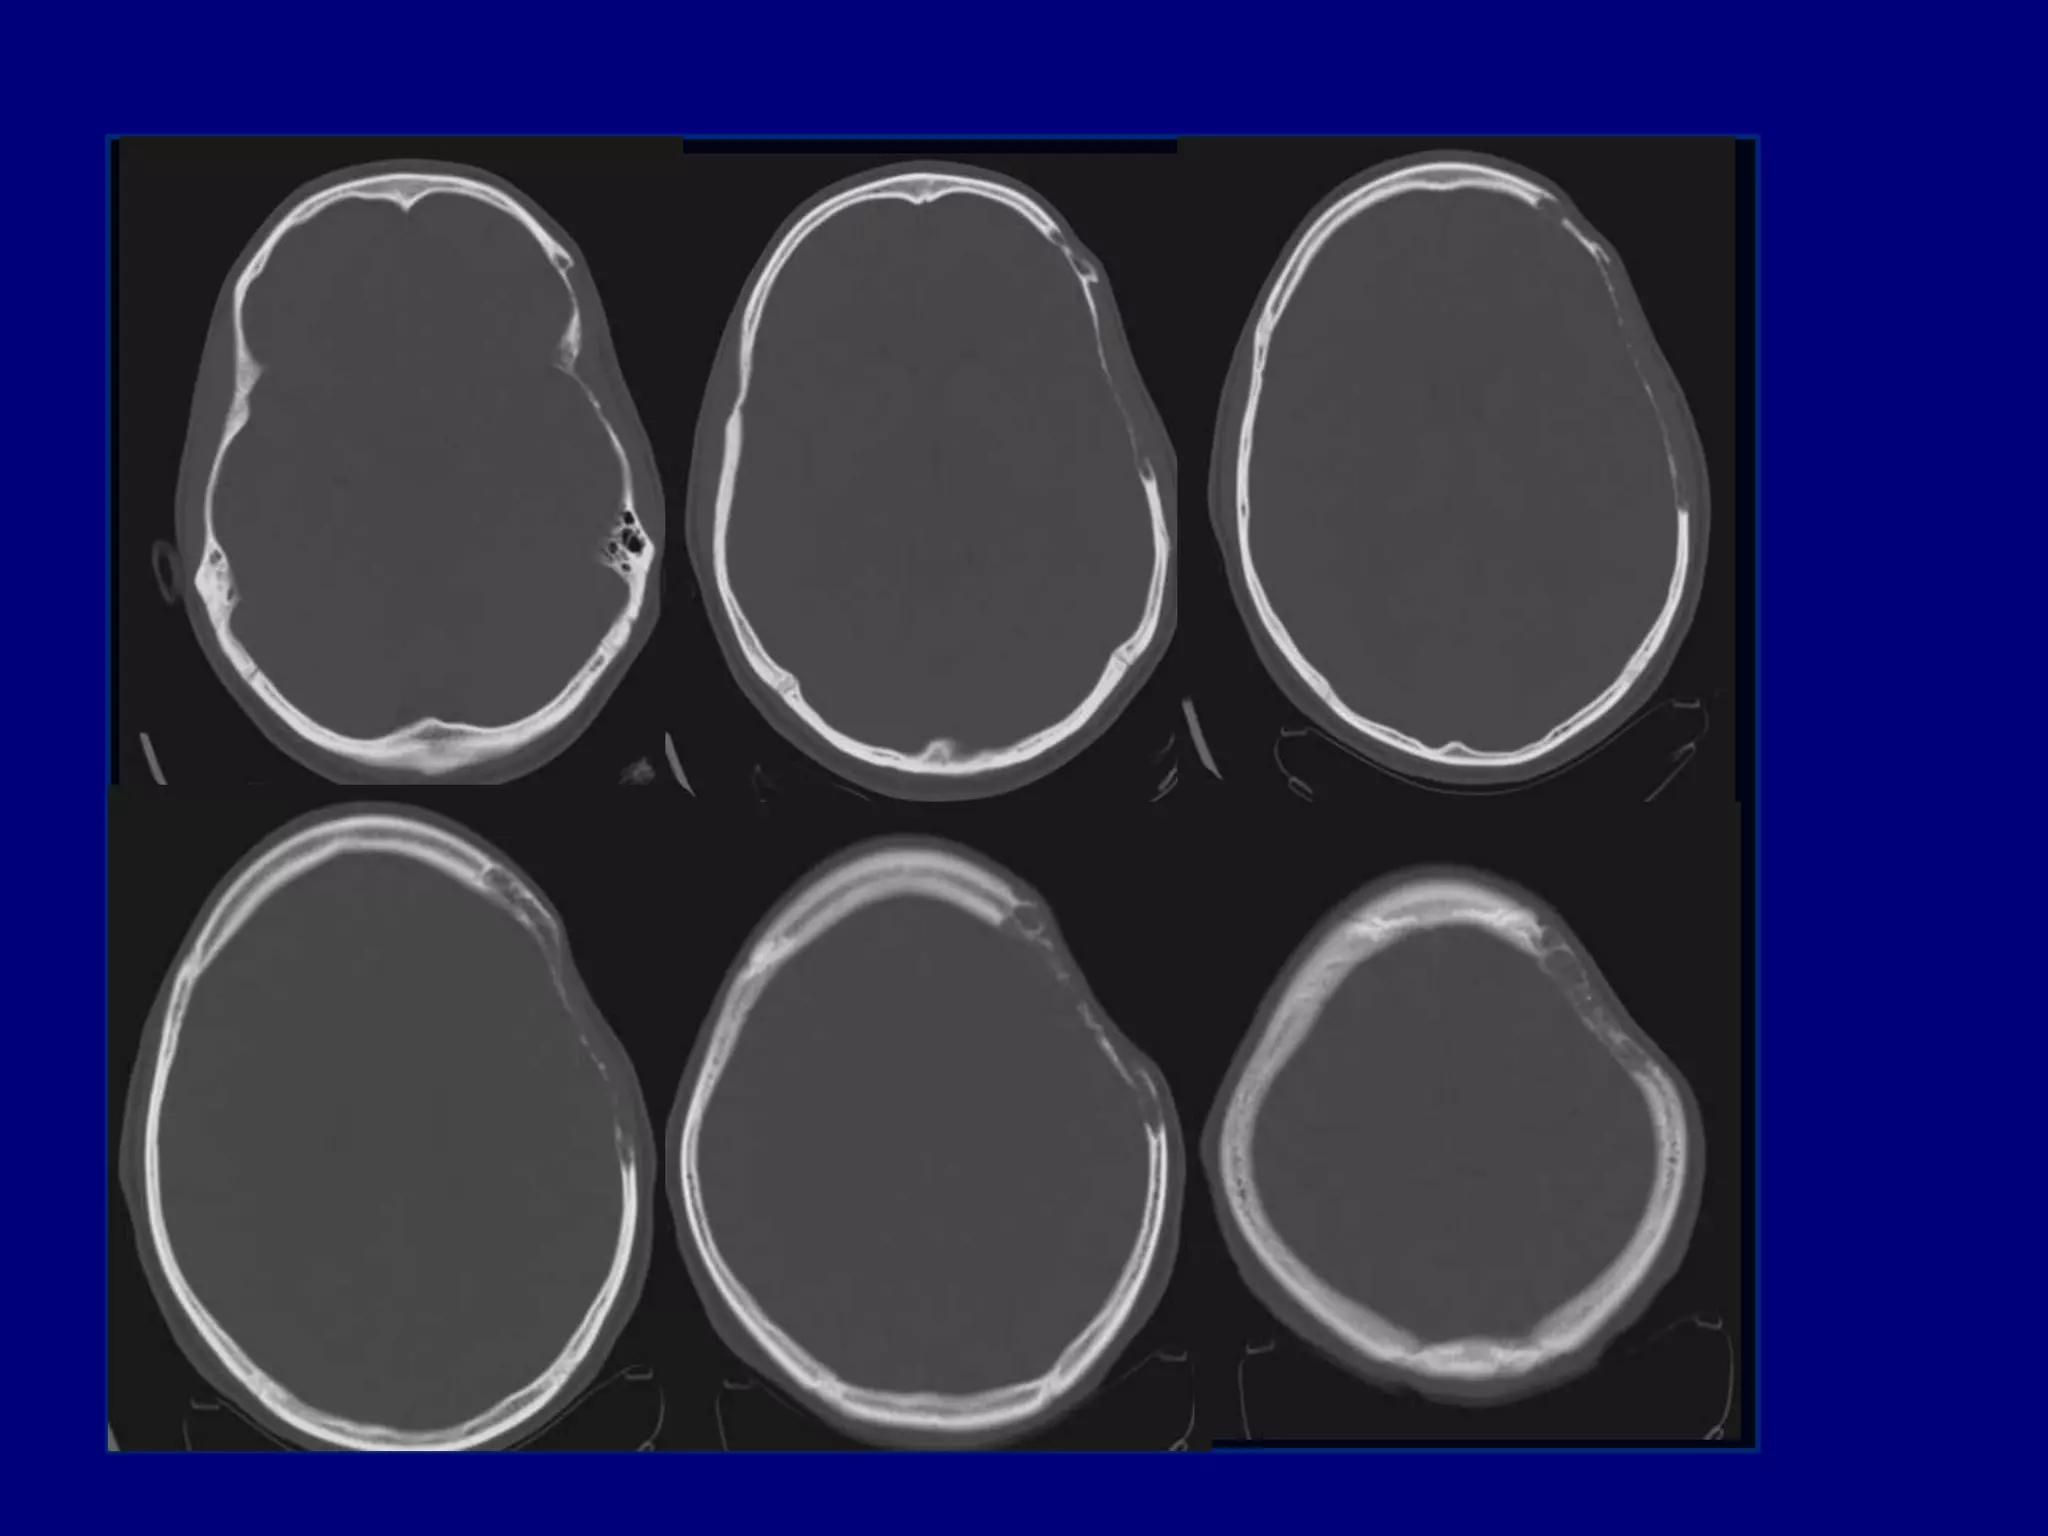

25-year old right handed man with complaints of

cranial defect left side of his head for three years



For the past 6 months he has had headaches in

the area of indentation, decreased hearing and

occasional visual problems

No history of fever, weight loss, systemic illness

or trauma

Computed Tomography

CT

Well defined skull defect with benign characteristics

 Thinning and disappearance of central portion and

absence of new bone formation